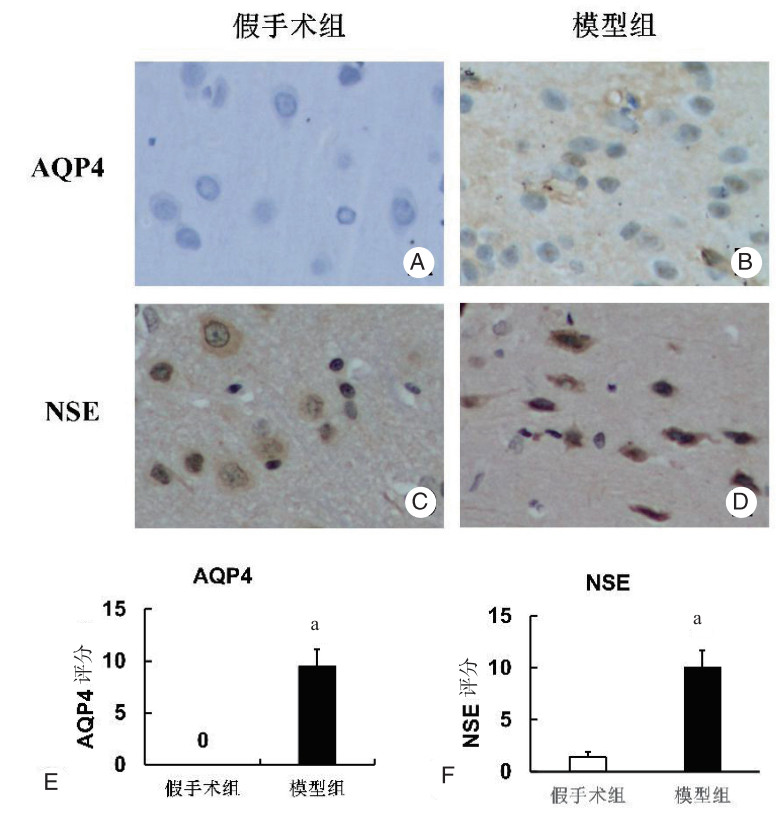

对假手术组及模型组大鼠模型脑组织进行AQP4及NSE免疫组织化学DAB显色(放大倍数200×),假手术组AQP4及NSE表达均为阴性,免疫组织化学评分为0分(图 3),模型组可AQP4及NSE表达较假手术组显著增加(P < 0.05,表 4)。

| A:假手术组AQP4抗体表达阴性,免疫组织化学为0分;B:模型组AQP4抗体表达阳性;C:模型组AQP4免疫组织化学评分显著明显高于假手术组(P < 0.05);D:假手术组NSE抗体表达阴性;E:模型组NSE抗体表达阳性;F:模型组NSE免疫组织化学评分显著明显高于假手术组(P < 0.05)。假手术组和模型组比较,a P < 0.05 图 3 对假手术组及模型组大鼠模型脑组织进行AQP4及NSE抗体免疫组织化学DAB显色(放大倍数200×),以及免疫组织化学评分 Fig 3 Brain tissues of rat models in the sham group and the model group were subjected to AQP4 and NSE immunohistochemical DAB color development (magnification 200×), and immunohistochemical score |